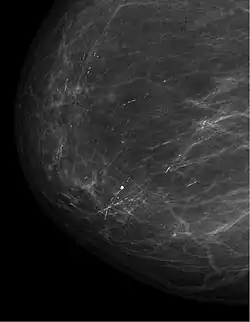

Differentialdiagnose und weitere Diagnostik

Wichtig ist, dass bei einer Mastitis non puerperalis ein Malignom nach Abheilung der Entzündung ausgeschlossen wird (Mammakarzinom, Paget-Karzinom, inflammatorisches Mammakarzinom).

Die periduktale Mastitis, auch plasmazelluläre bzw. granulomatöse Mastitis genannt, ist eine abakterielle und chronische Mastitis, die durch einen Sekretverhalt ausgelöst wird. Durch den Sekretverhalt kommt es zur Ektasie der Milchgänge mit übertreten des Sekretes in das umgebende Gewebe mit daraus resultierender Entzündungsreaktion. Betroffen sind vor allem Frauen mittleren Alters. Wichtig ist der Ausschluss eines Malignoms.